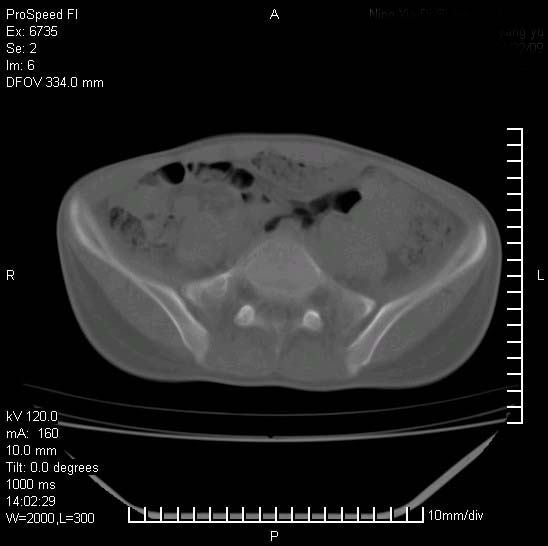

患者自诉胯部疼痛两年余,在当地服用中药,半月前至本院考虑骶髂关节结核,给予抗痨治疗。现发展至右下肢疼痛明显,活动受限,以膝关节处明显,拍膝关节平片无明显异常。

两侧骶骼关节改变,考虑强直性脊炎

左侧骶髂关节面限局性骨破坏,边缘硬化关节腔见钙化物;不出外tb

右侧骶髂关节也有类似改变,只是较左侧轻,首先考虑强直性脊柱炎,不除外结核,建议作hla-b27检查。

典型强脊炎改变,髋关节亦有累及

符合强直性脊柱炎表现。